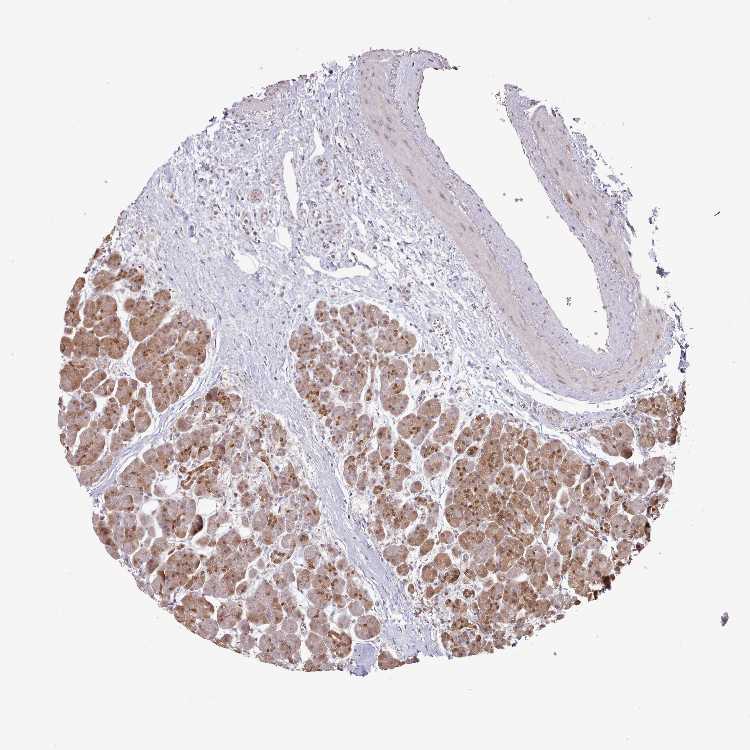

PANCREAS - Antibody stainingi

Antibody staining in the annotated cell types in the current human tissue is reported as not detected, low, medium, or high, based on conventional immunohistochemistry profiling in selected tissues. This score is based on the combination of the staining intensity and fraction of stained cells.

Each image is clickable and will lead to virtual microscopy that enables deeper exploration of all samples and also displays staining intensity scores, fraction scores and subcellular localization as well as patient and tissue information for each sample.

Antibody HPA041008Antibody HPA041307

Exocrine glandular cells MediumMedium

Pancreatic endocrine cells Not detectedMedium